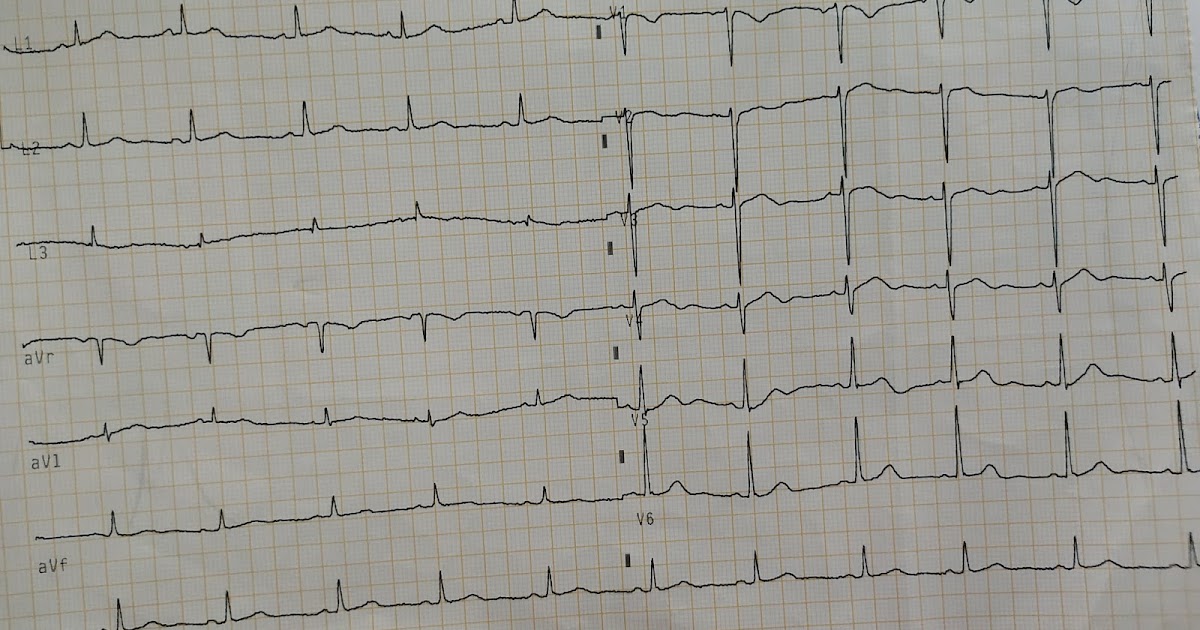

From ecgwaves.com